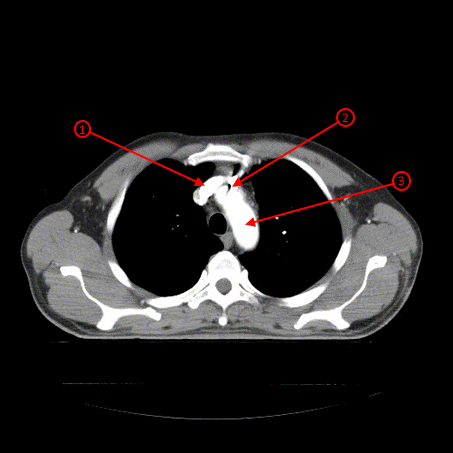

С целью дальнейшей верификации выполнили КТ ОГК и выявили, что инородное тело находится в дуге аорты.

Рисунок 2. КТ ОГК, на котором виден осколок, лежащий на дуге аорты.

1 — Инородное тело (осколок)

2 — Дуга аорты

С целью исключения экстравазации была выполнена МСКТ ангиография, по результатам которой данных за экстравазацию не было получено. Инородное тело находится между левой плечеголовной веной (интимное прилегание) и передней стенкой восходящего отдела грудной аорты (интимное прилегание). Расстояние до устья правой плечеголовной артерии составило 7,8 мм. Инородное тело округлой формы, размерами 9,7х10,6 мм.

Рисунок 3. МСКТ ангиография: осколок расположен на дуге аорты и левой плечеголовной вены.

1 — Левая плечеголовная вена

2 — Инородное тело (осколок)

3 — Дуга аорты